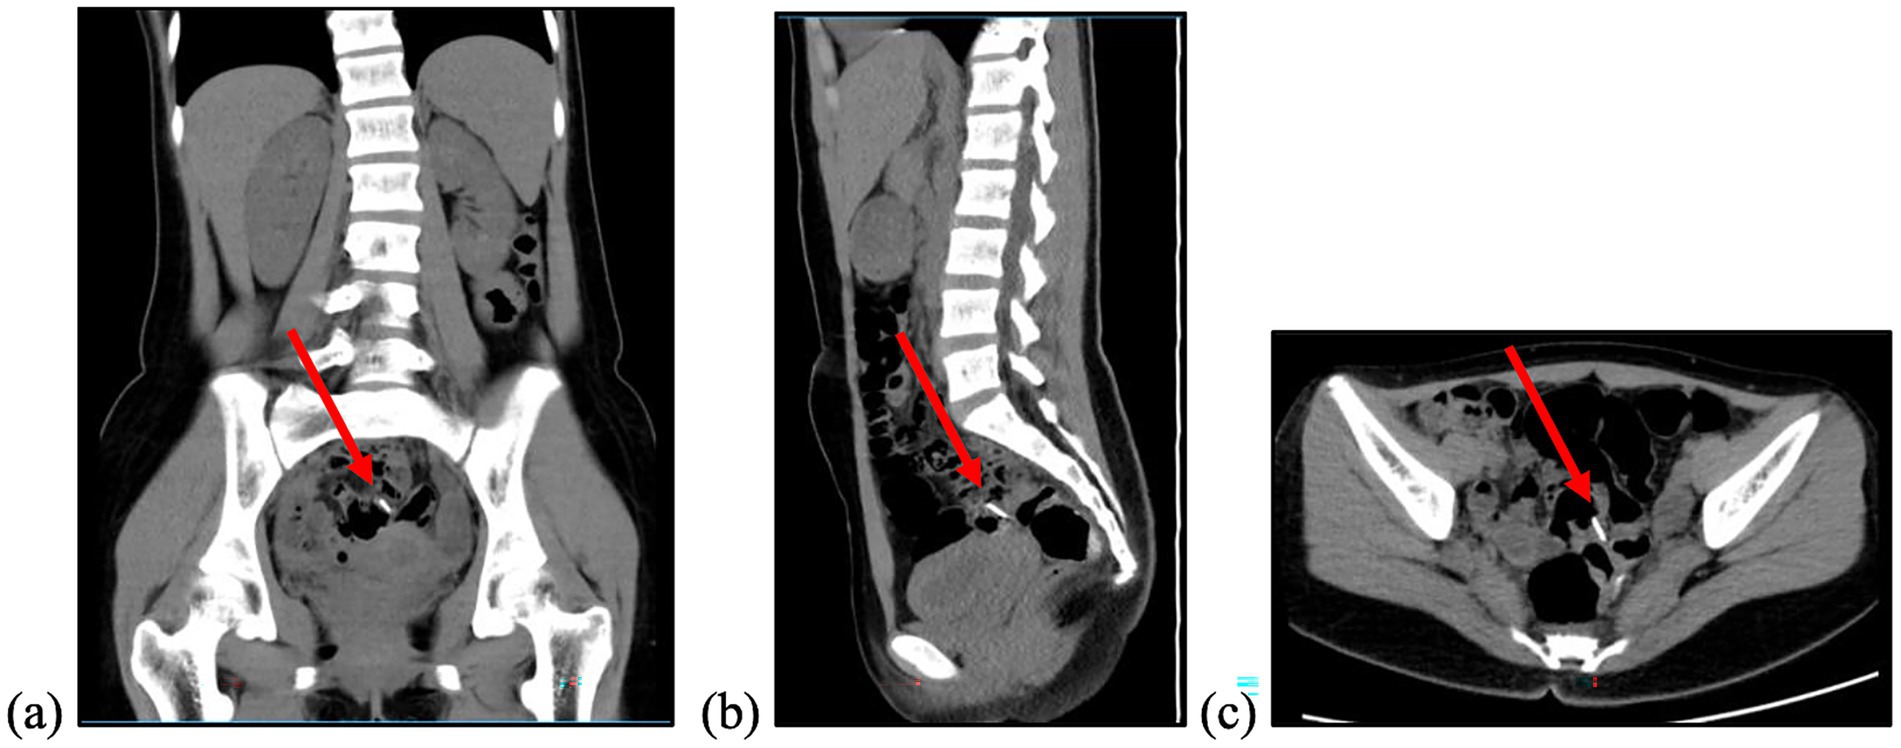

A colonoscopy conducted at the referring hospital yielded unremarkable findings throughout the lower gastrointestinal tract. Consequently, the patient was referred to our centre for further evaluation. Upon presentation, she reported no symptoms such as abdominal pain, distension, nausea, vomiting, fever, or rectal bleeding, and had no significant past medical history. She was alert, hemodynamically stable, and an abdominal examination revealed normal bowel sounds. Mild tenderness was noted in the right iliac and hypogastric regions without any signs of peritoneal irritation. A repeat endoscopic assessment in our facility revealed several metallic reflections embedded within the intestinal mucosa. Contrast-enhanced abdominal computed tomography (CT) confirmed the absence of gastrointestinal perforation, pinpointing the foreign object in the distal ileum (Figure 2).

Figure 2. Abdominal CT Scan with contrast performed on Day 23 after ingestion showed a foreign body (red arrow) within the projection of the minor pelvis, within the ileum. (a) Coronal view; (b) sagittal view; (c) axial view.